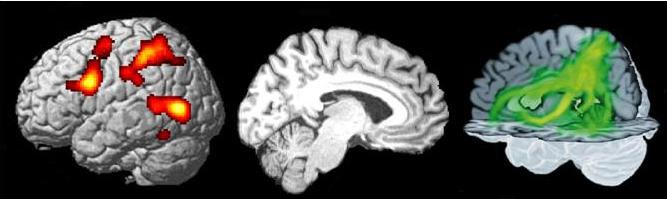

Während Sie im MRT-Gerät liegen, werden Sie je nach Studie gebeten, eine oder mehrere Aufgaben durchzuführen. Die jeweilige Aufgabe wird Ihnen vor Beginn der Untersuchung ausführlich erklärt. Dabei handelt es sich meistens um Studien zu speziellen Bewegungen, Aufmerksamkeit, Sprachverarbeitung oder Arbeitsgedächtnis. Während Sie diese Aufgaben durchführen, nehmen wir Bilder Ihres Gehirns auf, um später herausfinden zu können, welche Hirnareale an der Aufgabe beteiligt waren.

Zusätzlich werden je nach Studie neben diesen so genannten „funktionellen“ auch strukturelle bzw. anatomische Aufnahmen Ihres Gehirns gemacht. Für diese Messung müssen Sie lediglich ganz entspannt auf dem Rücken liegen bleiben.